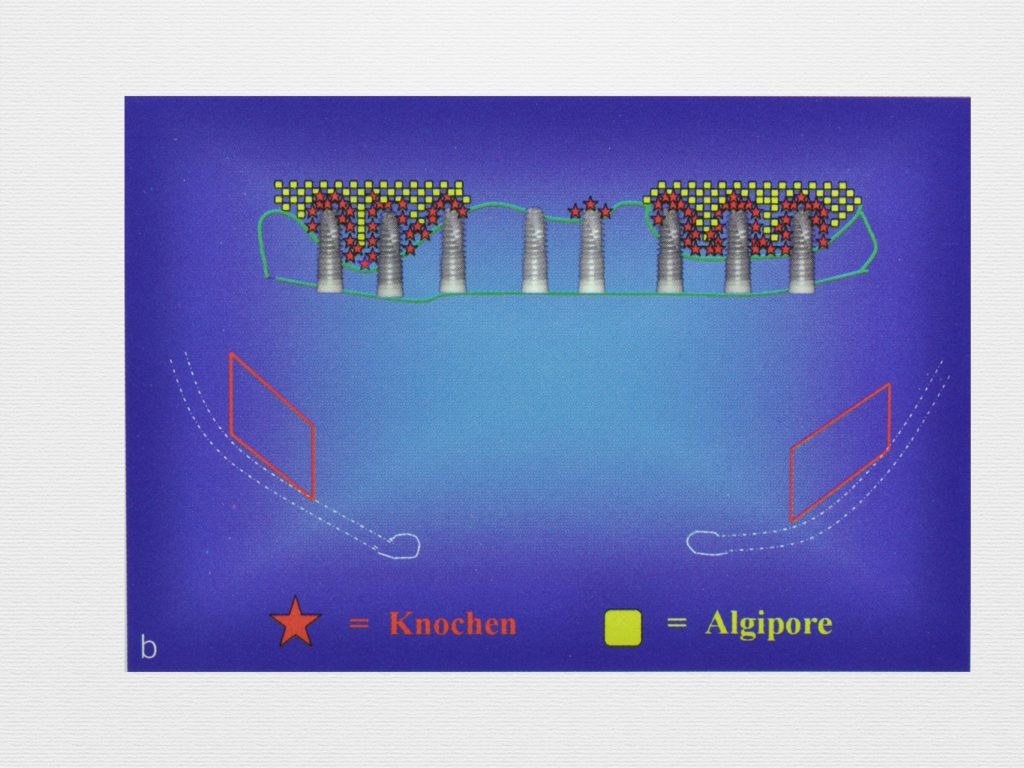

Принцип направленной костной регенерации. Костная регенерация под защитой мембраны Биоматрикс

Принцип направленной костной регенерации. Костная регенерация под защитой мембраны Биоматрикс

Принцип направленной костной регенерации. Костная регенерация под защитой мембраны Биоматрикс